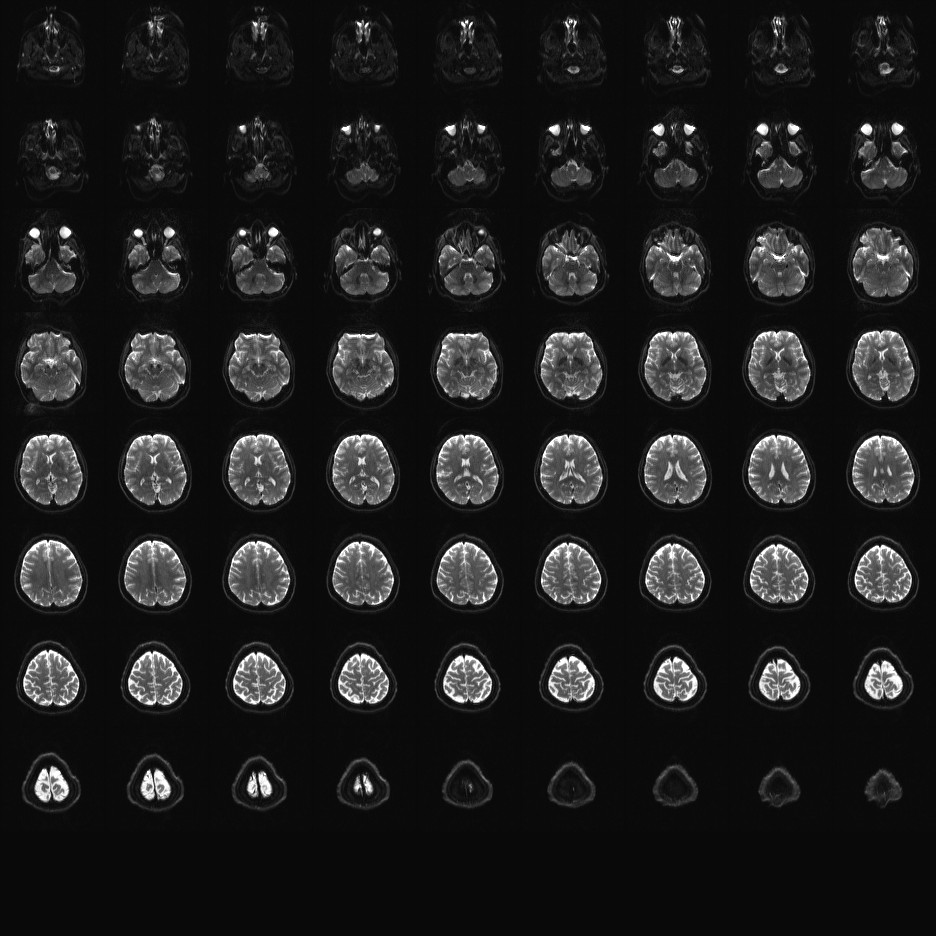

Multi-banded RF pulses can be used to accelerate volume coverage along the slice direction by simultaneously exciting and acquiring multiple slices and subsequently unaliasing them using parallel imaging principles and the spatial information available in multi-channel RF array coils.

This allows for a direct reduction in the volume TR by the number of simultaneously excited slices (i.e., the multiband (MB) factor or the slice acceleration factor).